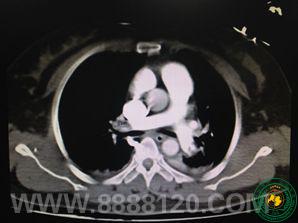

宜宾二医院重症医学科成功救治一例肺栓塞伴呼吸心跳骤停患者

宜宾二医院重症医学科成功救治一例肺栓塞伴呼吸心跳骤停患者6810